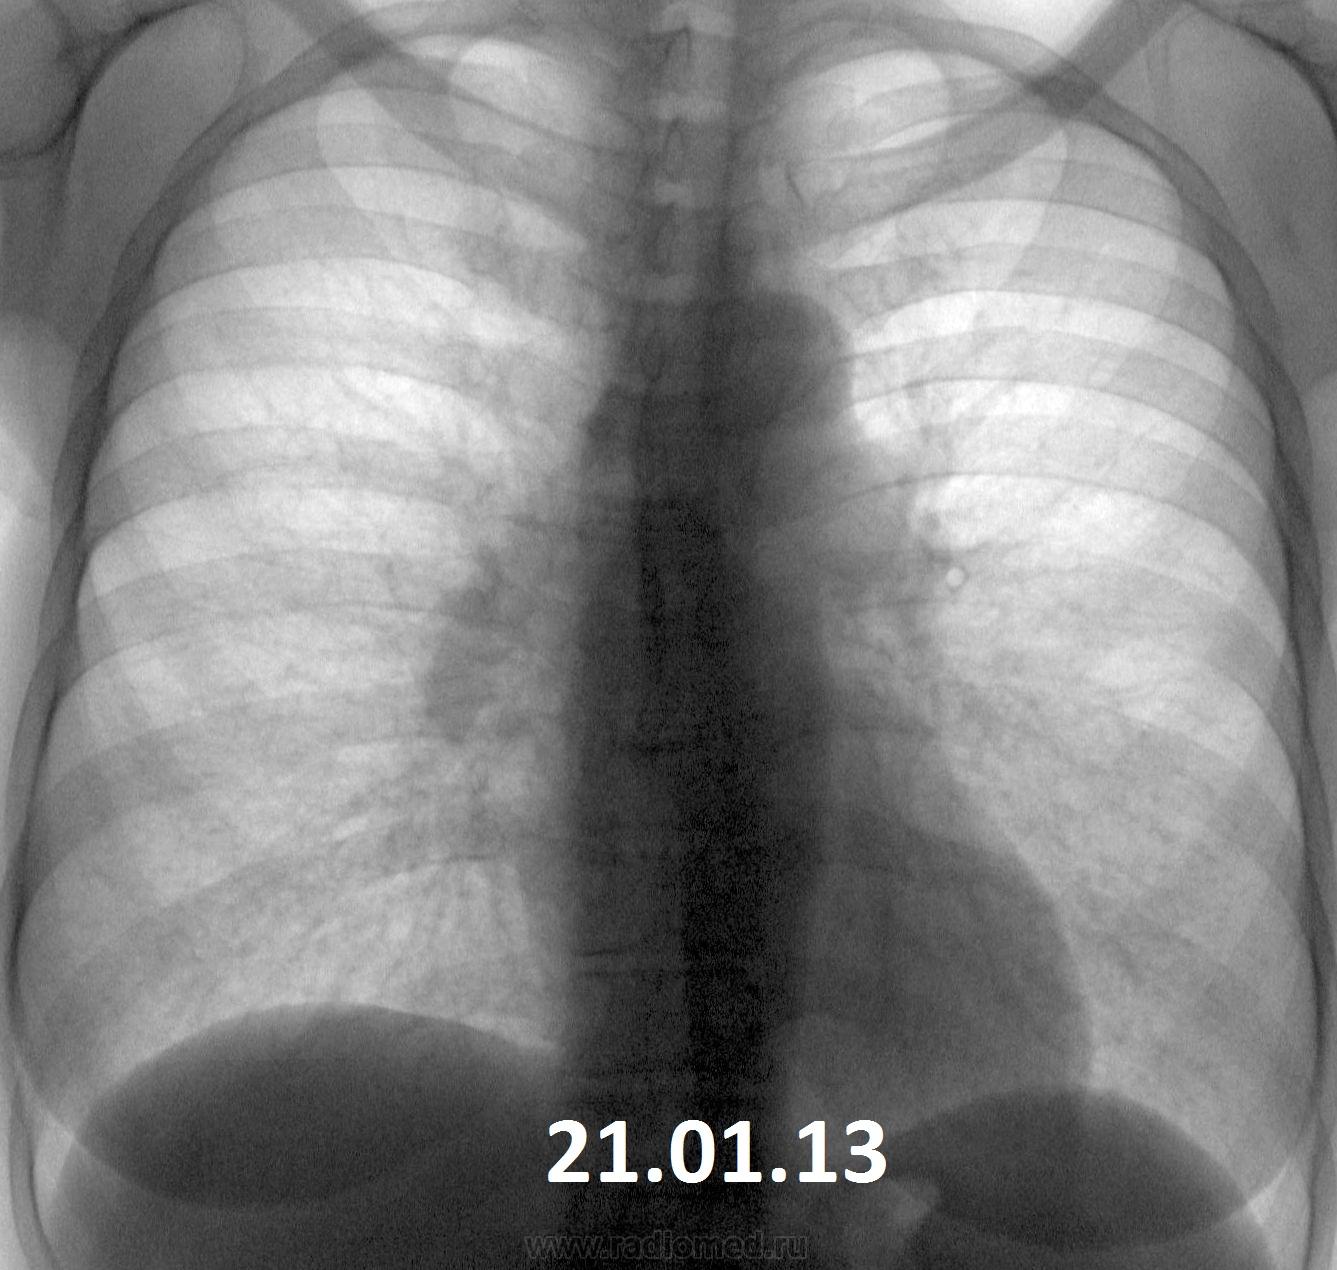

Два дня назад читал флюшки, показалось через чур много узелковых теней на фоне усиленного рис. Жалоб на "легкие" нет, но плохие анализы по "почкам". У мужа был (то ли умер, то ли развелась) ТБС. Придираюсь?

Похоже, не придираетесь. Очаги есть, диффузная деформация рисунка есть. Слоить надо.

Очагов как таковых не вижу, а медленно прогрессирующее изменение л/рисунка в средненижних отделах с преобладающим интерстициальным компонентом, по-моему, на лицо. +небольшая (возможно, кажущаяся) динамика расширения корня правого легкого. К норме отнести сложно. Нужен анамнез, исследование функции внешнего дыхания.

Изменены корни. Вероятней всего сердечные проблемы и изменение ЛР с этим и связано. Какой хоть возраст?

Женщина 1958 г.р., профилактическая флгр., жалоб на ОГК не предъявляет. Есть же изменения в легких при заболевании почек, или эта картина никак к этому не лезет?

P.S. Не знаю почему, но на флюорографе - картина явно разнится м-ду годами, а за процедурами  сжатий и обработок изображений - изюминки потерялись.

А отчего бы не быть саркоидозу???

+1...очень похоже на медиастинально-легочную форму. Игорь Иванович, лучше перестрахуйся консультацией в ОТД.

Саркоидоз ВГЛУ и легких